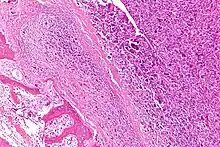

Histopathology of osteosarcoma, showing tumor cells with high nuclear pleomorphism, but relatively less so in cells entrapped in neoplastic bone matrix (appearing pink on this H&E stained slide).

Microscopically: The characteristic feature of osteosarcoma is presence of osteoid (bone formation) within the tumor. Tumor cells are very pleomorphic (anaplastic), some are giant, numerous atypical mitoses. These cells produce osteoid describing irregular trabeculae (amorphous, eosinophilic/pink) with or without central calcification (hematoxylinophilic/blue, granular)—tumor bone. Tumor cells are included in the osteoid matrix. Depending on the features of the tumor cells present (whether they resemble bone cells, cartilage cells, or fibroblast cells), the tumor can be subclassified. Osteosarcomas may exhibit multinucleated osteoclast-like giant cells.[22]